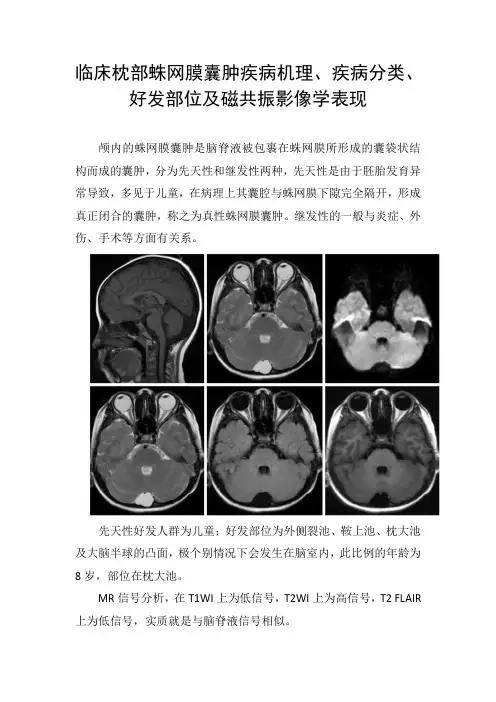

颅内的蛛网膜囊肿是脑脊液被包裹在蛛网膜所形成的囊袋状结构而成的囊肿,分为先天性和继发性两种,先天性是由于胚胎发育异常导致,多见于儿童,在病理上其囊腔与蛛网膜下隙完全隔开,形成真正闭合的囊肿,称之为真性蛛网膜囊肿。

继发性的一般与炎症、外伤、手术等方面有关系。

先天性好发人群为儿童;好发部位为外侧裂池、鞍上池、枕大池及大脑半球的凸面,极个别情况下会发生在脑室内,此比例的年龄为8岁,部位在枕大池。

MR信号分析,在T1WI上为低信号,T2WI上为高信号,T2 FLAIR 上为低信号,实质就是与脑脊液信号相似。